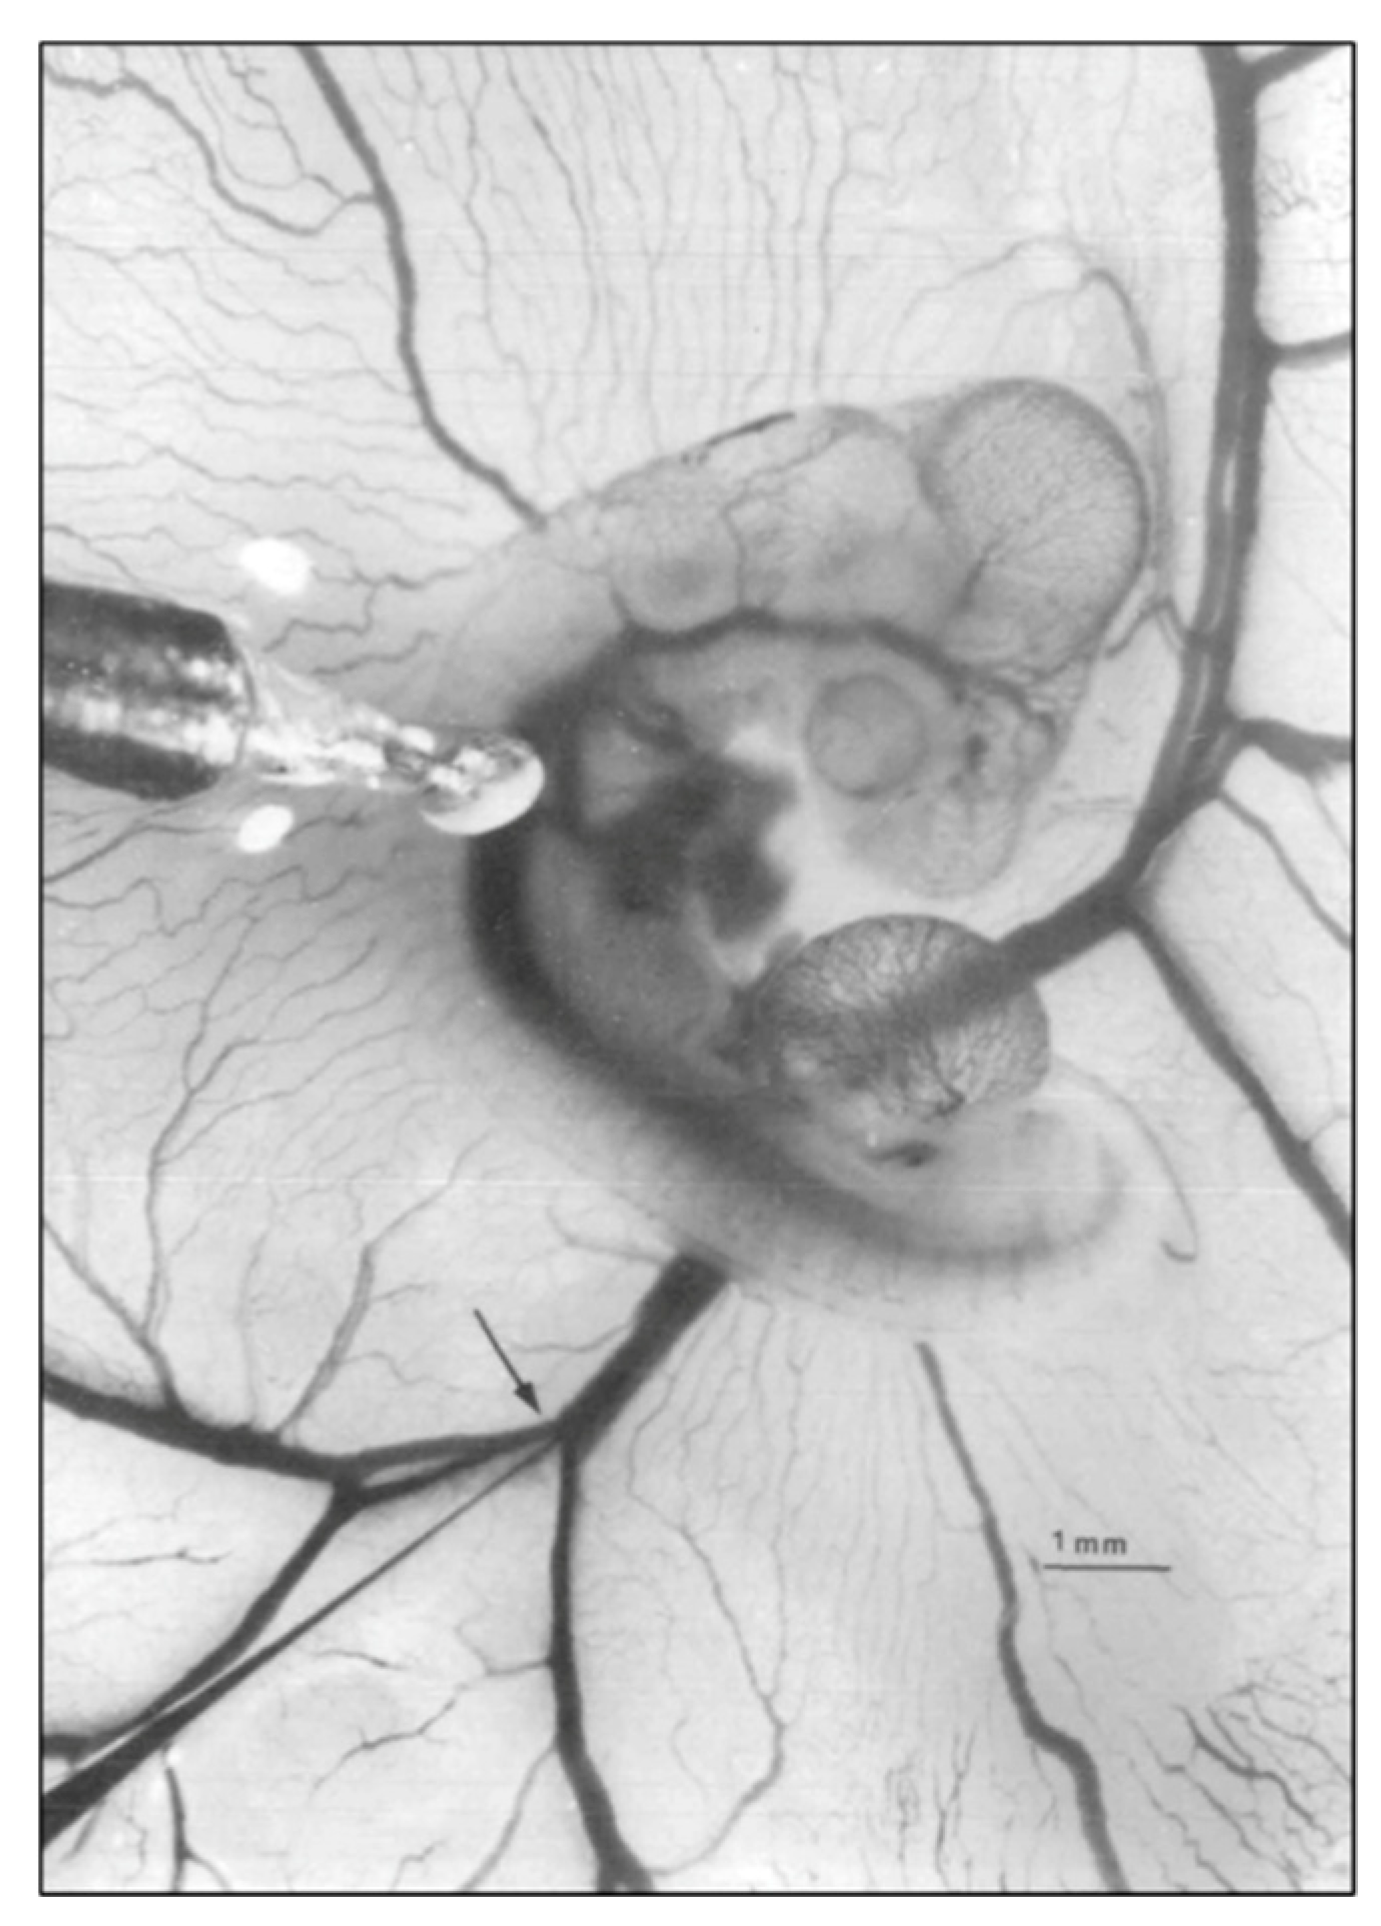

- Reckova, M.; Rosengarten, C.; deAlmeida, A.; Stanley, C.P.; Wessels, A.; Gourdie, R.G.; Thompson, R.P.; Sedmera, D. Hemodynamics is a key epigenetic factor in development of the cardiac conduction system. Circ. Res. 2003, 93, 77–85. [Google Scholar] [CrossRef]

- Hall, C.E.; Hurtado, R.; Hewett, K.W.; Shulimovich, M.; Poma, C.P.; Reckova, M.; Justus, C.; Pennisi, D.J.; Tobita, K.; Sedmera, D.; et al. Hemodynamic-dependent patterning of endothelin converting enzyme 1 expression and differentiation of impulse-conducting Purkinje fibers in the embryonic heart. Development 2004, 131, 581–592. [Google Scholar] [CrossRef]